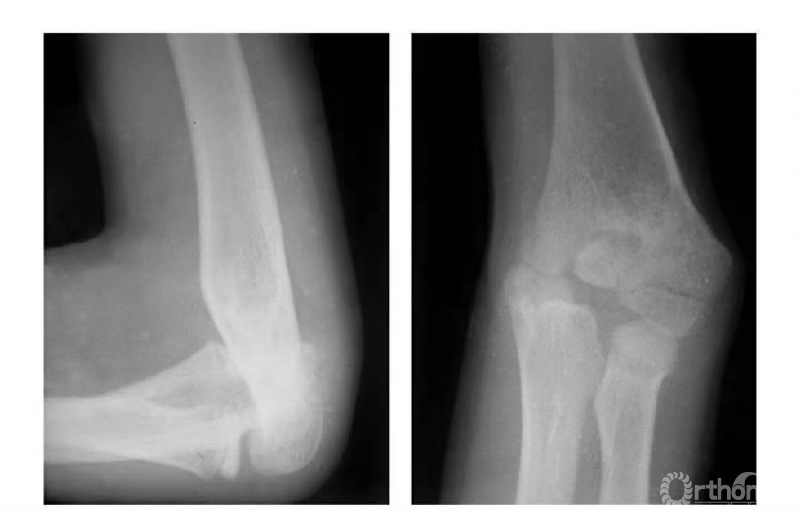

例4:肱骨内髁滑车骨折,且骨块内移,致骨骺因损伤而早闭,并形成肘内翻畸形(图7)。

图7

例5:肱骨内髁外侧壁骨骺因损伤而早闭,而内外侧骨骺继续生长致滑车沟变深,继而肱骨下端形成鱼尾状畸形(图8)。

图8